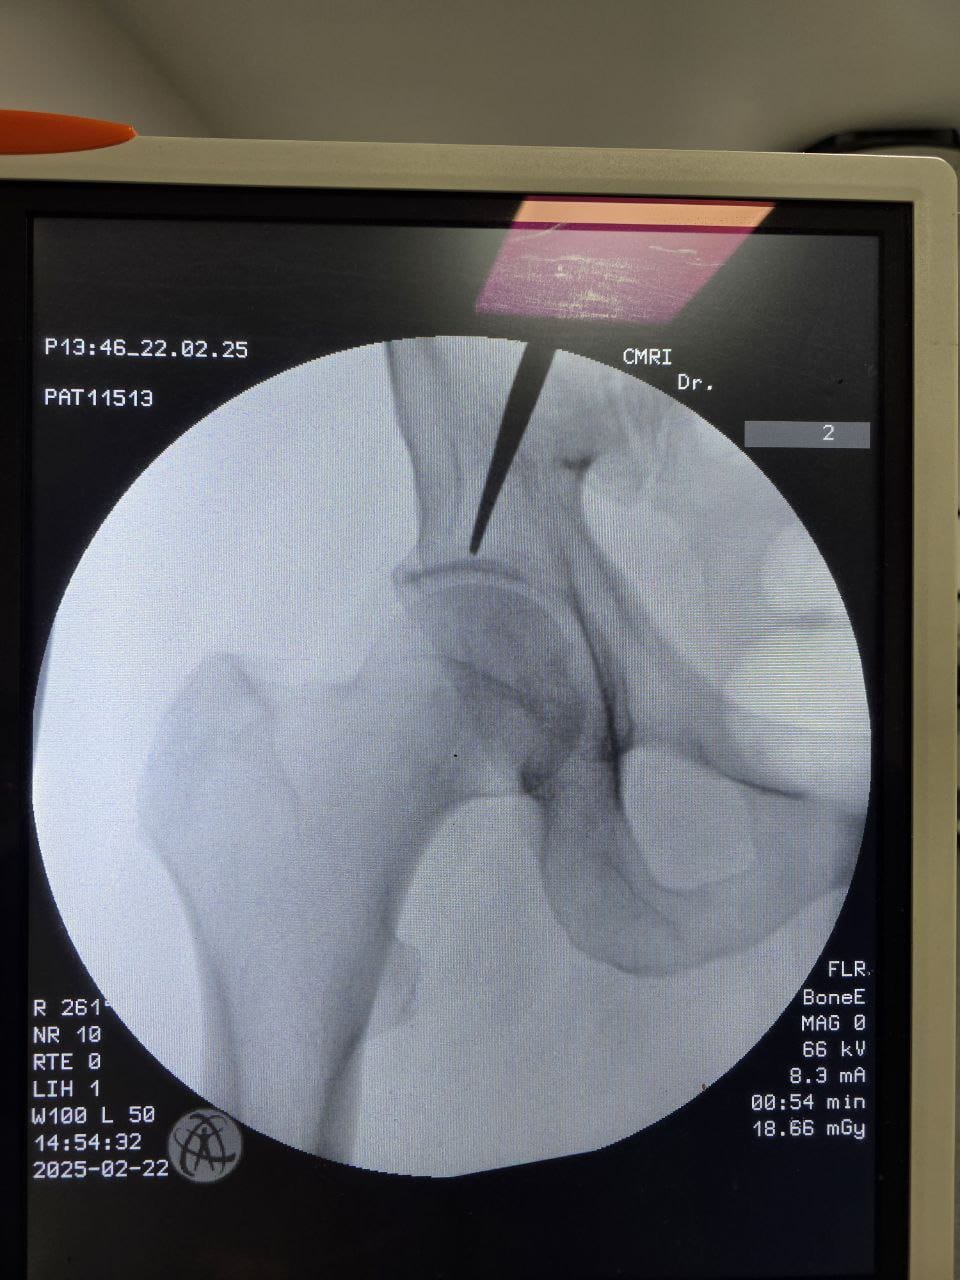

Procedures

Struggling with chronic pain? Get advanced, personalised pain management from Dr. Manish De, one of Kolkata’s leading pain specialists. From knee pain, heel pain, low back pain, frozen shoulder, migraines, cancer pain to post-TKR persistent pain—Dr. De offers safe, evidence-based treatments across multiple locations: